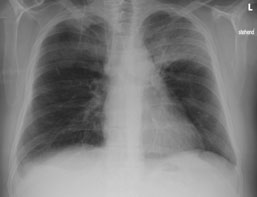

Einer Ihrer Patienten wird wegen einer Pneumonie seit 10 Tagen antibiotisch behandelt. Sie veranlassen eine Thoraxröntgen zur Verlaufskontrolle.

Hier sehen Sie das Kontrollröntgen:

Thorax pa

Bild vergrössern

Wie beurteilen Sie das aktuelle Thoraxröntgen (mehrere richtige Antworten möglich):